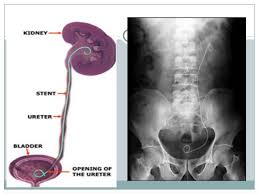

DJ stent is the short form for Double “J’ stent. It is a small tube that is placed in the body from the Kidney to the Urinary bladder. It is kept for about six weeks. The lower portion which is in the Urinary bladder is shaped like a usual “J” while the upper portion is like a mirror image. The shape helps in retaining the stent in the body.

The DJ stenting could be carried out under spinal anesthesia cystoscope is used for the procedure. First a guide wire is passed through the ureter to the Kidney. The DJ stent is then passed over the guide wire and pushed in using a pusher.